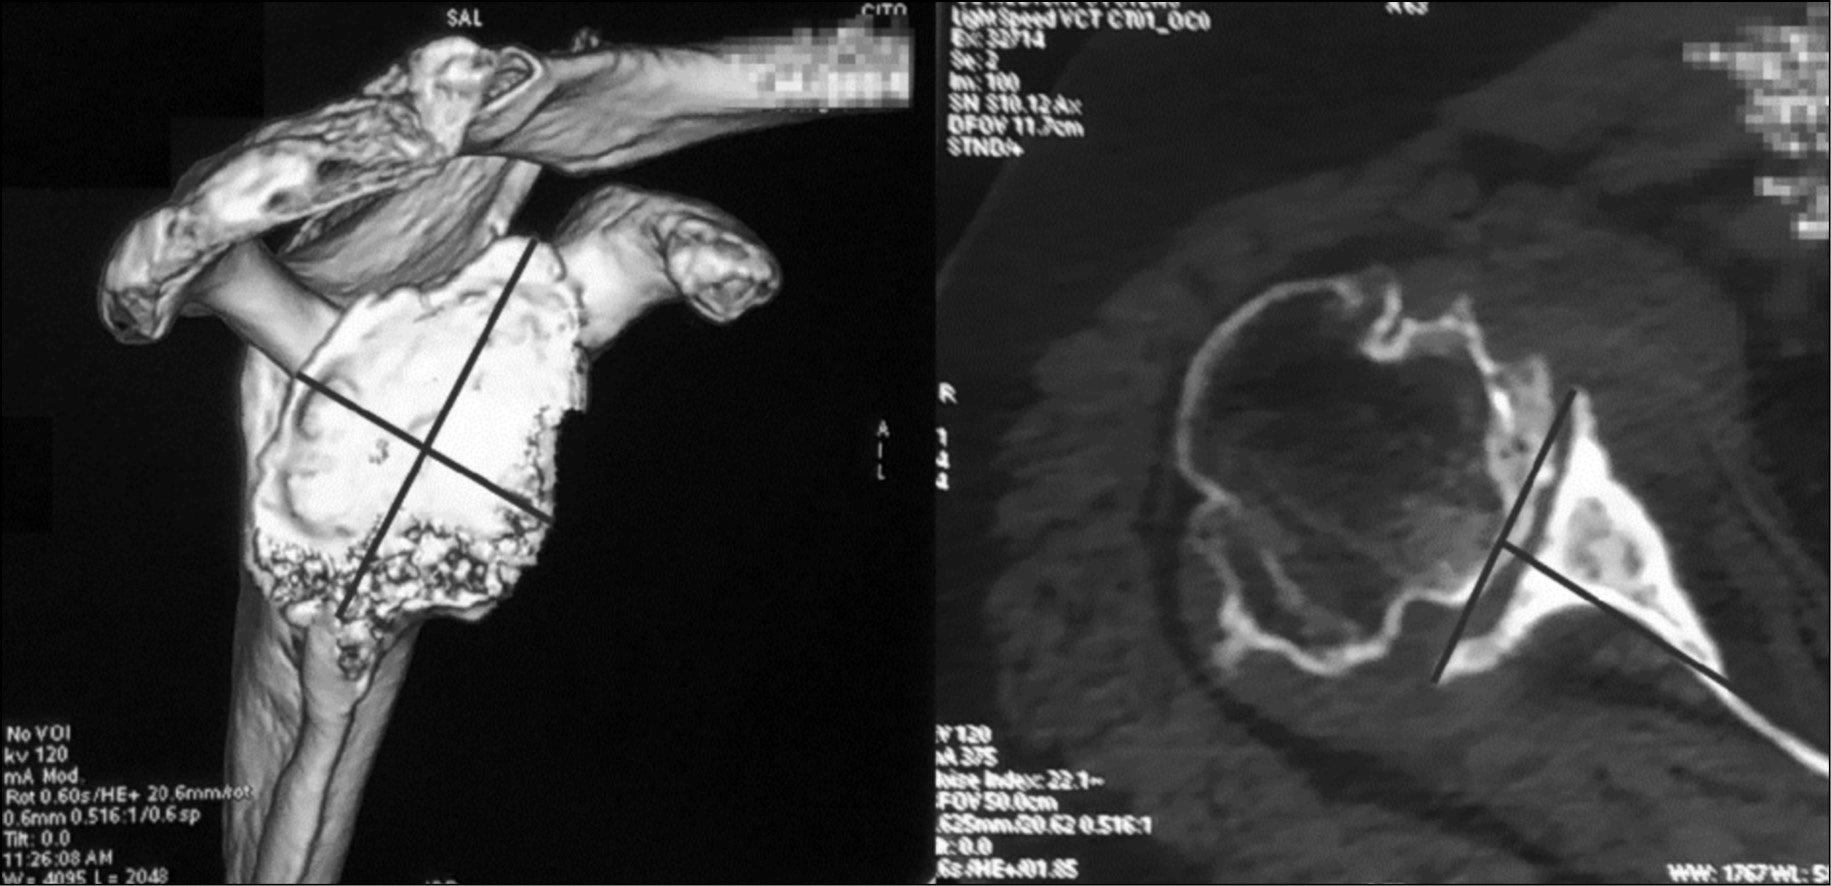

Clinical, radiological, and instrumental examinations of the patients were performed before the surgery. A clinical examination, including assessment of the pain syndrome, range of joint motion, and functional state of the deltoid muscle, was performed. With severe hypotrophy of the deltoid muscle, which often results from injuries, especially preceding surgical treatment, ultrasound examination of the deltoid muscle and electroneuromyography of the upper limb nerves were performed. With total atrophy of the deltoid muscle bundles, even reverse arthroplasty is functionally unpromising. Radiography of the shoulder joint in two projections and multispiral computed tomography of the shoulder joint with visualization of the glenoid were performed to assess its dysplasia and defects (Fig. 1). These diagnostic methods are required for planning the preferred types of endoprosthesis components and their spatial orientation during implantation.

Fig. 1. Computed tomography was performed to measure anatomical parameters of the articular process of the scapula